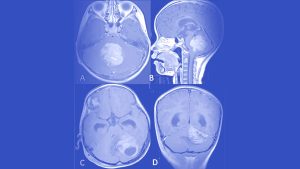

تومور مخچه مدولوبلاستوما

مدولوبلاستوما (Medulloblastoma) یک تومور مغزی سرطانی (بدخیم) است که از مخچه ، یعنی بخش پشتی و پایینی مغز که مسئول هماهنگی عضلات، تعادل و حرکت است،